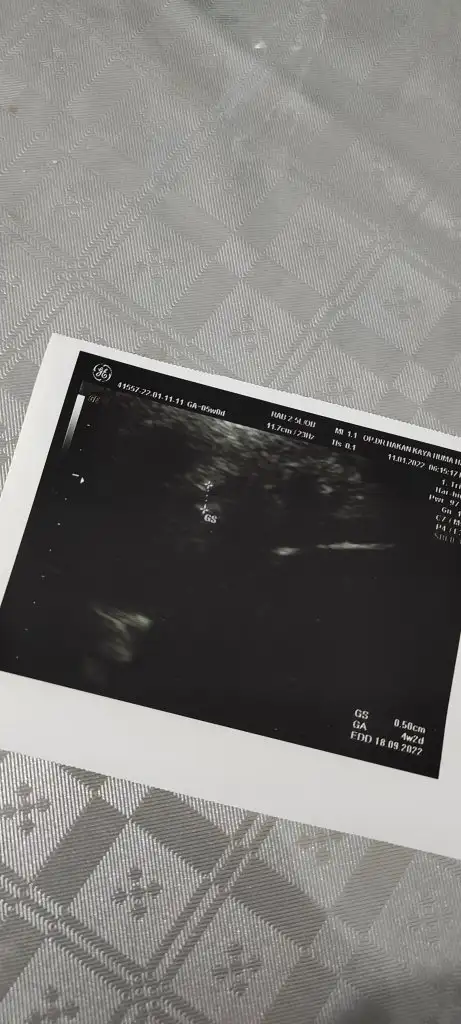

Keseyi gördük,keseye göre 4+2 dedi nöbetçi doktor

Miniminnacik

Düşük önleyici iğne yazdi onu yaptırdık lekelenme olur ama takipte kal rahim icine yerlesmis minik dedi![]()

Ya hala lekelenme görüyorum normal her gebelik farkli dedi kimi hic gormez kimi 6-7 haftada görür orneklendirdi hepAyy cok sukurler olsun rabbim

Şükür teyzesi,3 boyutlu olunca gözüktü yoksa yine gozukmezdi

Daha cok minnakmis bak demek o yuzden gozukmemis